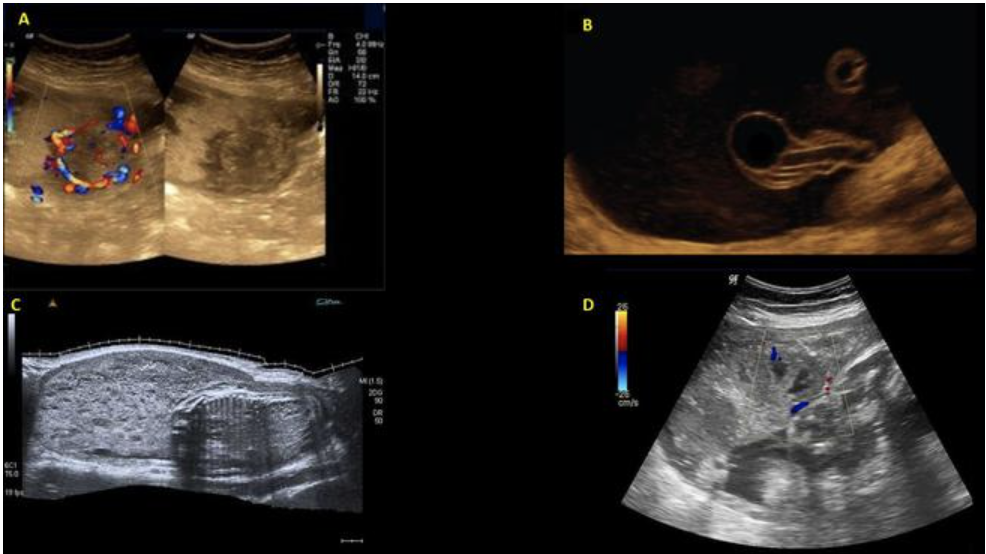

chorioangioma is supected. which image shows it

a) A

b) B

c) C

d) D